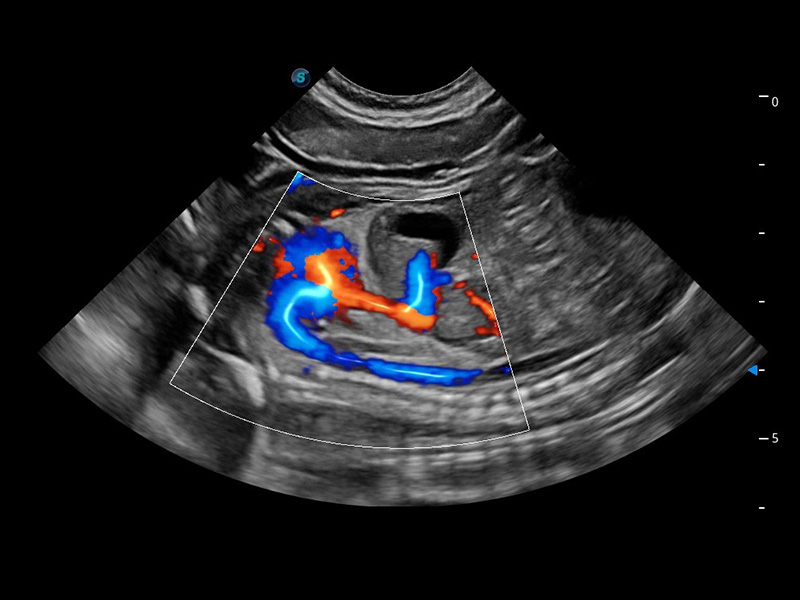

ProPet 60 作为一款高端台式动物超声设备,为动物医生的日常诊断提供了一系列贴合动物临床需求、解决临床实际问题的高级成像功能。凭借全系列高清探头,满足医生对腹部、心脏、生殖、浅表、肌骨等成像的所有需求,切实帮助您提升检查效率,提高诊断信心。

兽用彩色多普勒超声诊断系统

动物是人类最亲密的朋友和最值得信赖的伙伴。银河优越会也一直致力于探索动物专用的超声影像解决方案。 全新推出的ProPet系列,是银河优越会在动物超声影像智能化、专业化、精准化的一次跨越式革新。动物不能用言语来表述自己的不适,通过超声影像,ProPet系列搭建了动物医生与不同物种沟通的“桥梁”,为动物医生注入了“治愈之力”。